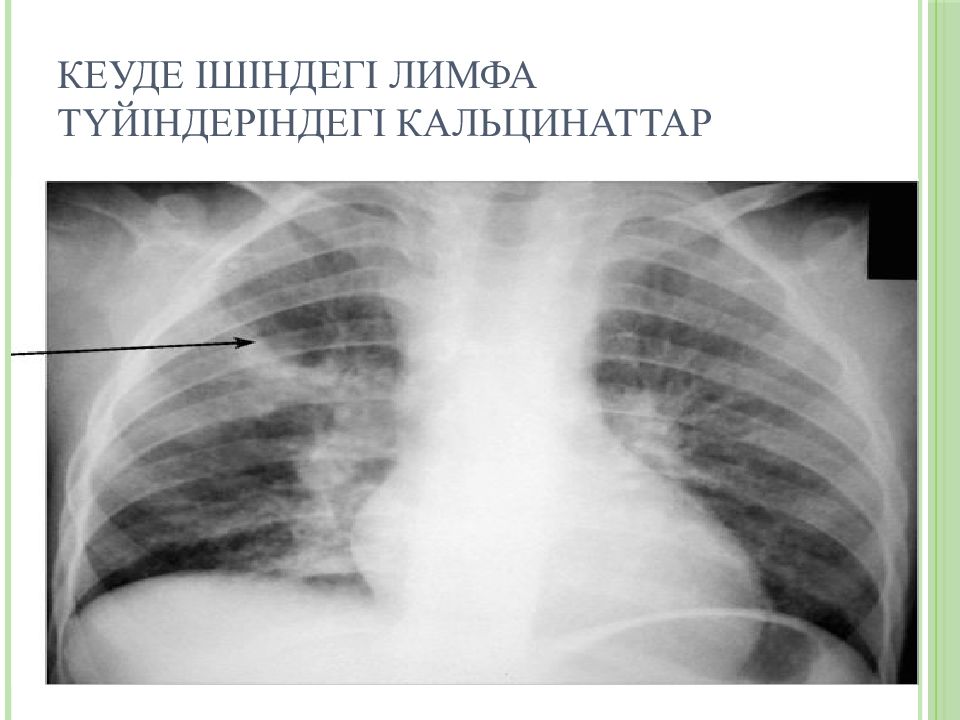

Симптомы и лечение инфильтративного туберкулеза легких

Раздел: Снимки-откровения